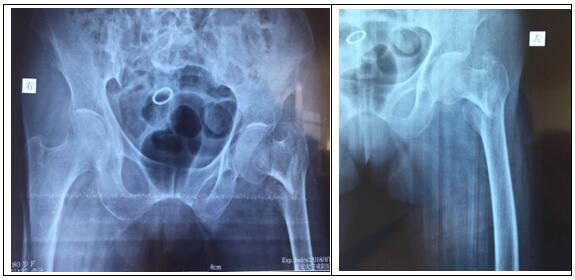

患者房某,80岁,女。因摔伤致左髋部疼痛,左下肢负重功能障碍,由外院转入我院骨一科。确诊为:左侧股骨转子间骨折。

图片一:(术前照片)